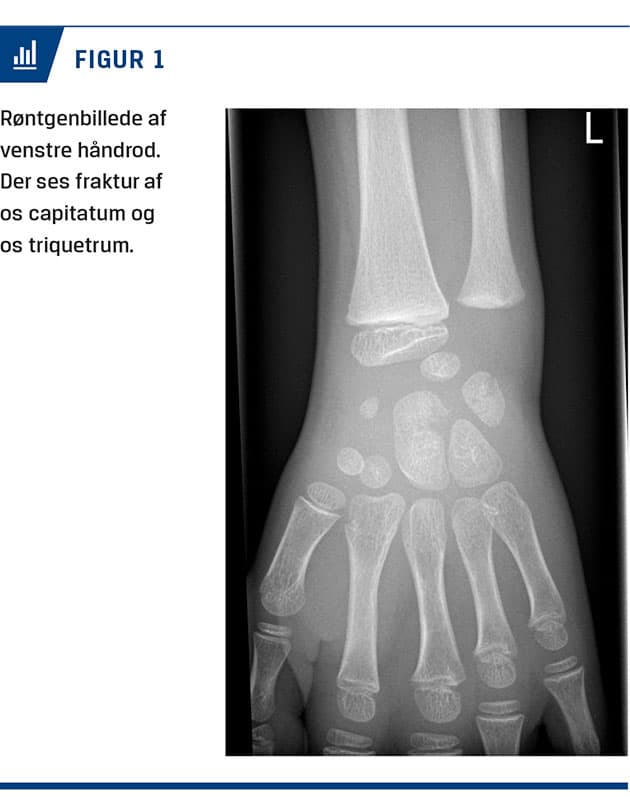

En syvårig dreng blev behandlet på skadestuen efter at have fået klemt venstre hånd mellem kanten af et skolebord og gulvet. Ved en objektiv undersøgelse fandt man misfarvning både dorsalt og volart over håndroden. Han var tydeligt smertepåvirket ved både direkte og indirekte undersøgelse af håndroden. Bevægeligheden i hånden var ophørt pga. smerter. En røntgenoptagelse viste fraktur af os capitatum og os triquetrum (Figur 1). Samme dag blev der foretaget CT af venstre hånd for verificering af diagnosen samt udelukkelse af øvrige frakturer og dislocering med betydning for behandlingen (Figur 2). Frakturerne i os capitatum og os triquetrum var udislocerede og egnede til konservativ behandling. Der blev anlagt en dorsal gipsskinne. Ved ambulant kontrol syv dage posttraumatisk var der bedring smertemæssigt. En røntgenoptagelse viste uændret stilling af frakturerne. Ved ambulant kontrol fire uger efter traumet viste en røntgenoptagelse begyndende kalcifikation af frakturen, klinisk var der smertefrihed. Patienten blev henvist til ergoterapi. Efter seks måneder havde han normal bevægelighed og god kraft i

håndroden ved belastning.